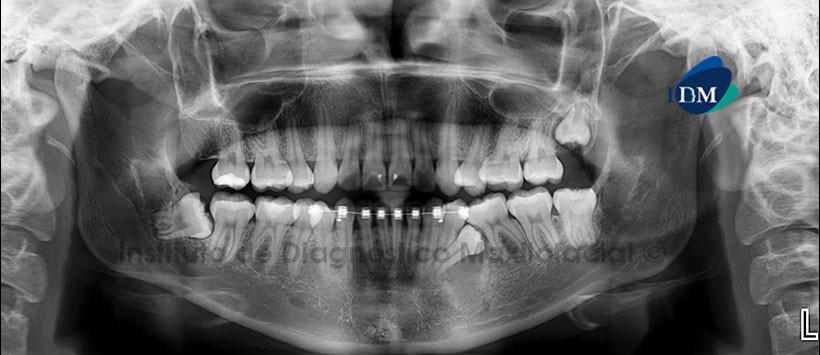

Paciente femenino, 20 años de edad acude al Instituto de Diagnóstico Maxilofacial (IDM) para su evaluación previo a tratamiento de ortodoncia.

A la evaluación de la radiografía panorámica (Figura1) observamos a la pieza 3.5 impactada en posición disto angular sobre la cara mesial de la pieza 3.6, donde apreciamos a una imagen radiolúcida de limites bien definidos que compromete el reborde alveolar y se extiende hacia la basal correspondiente. Así mismo presenta aparatología fija para ortodoncia de la 3.4 a la 4.4.

Al estudio mediante tomografía computarizada de haz cónico (CBCT) en cortes axiales (Figura 2) y coronales (Figura 3) se evidencia que la imagen antes descrita expande ligeramente la tabla tablas ósea vestibular y desplaza a la pieza 3.5 hacia lingual (a nivel del tercio medio radicular). El tercio apical presenta dilaceracion hacia caudal y la porción coronal se encuentra hacia la tabla vestibular